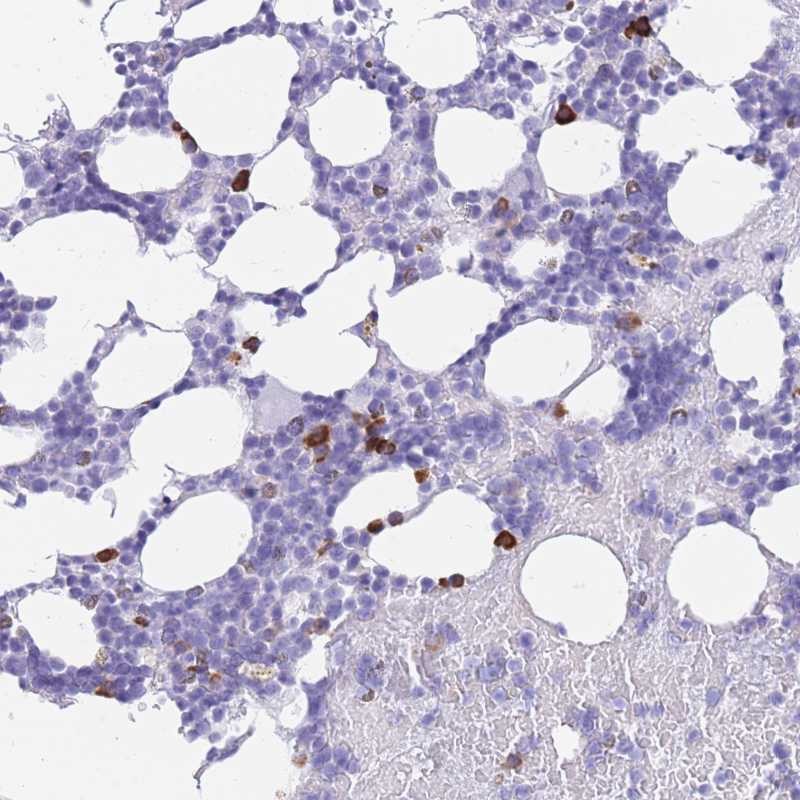

Immunohistochemical staining of human bone marrow shows strong cytoplasmic positivity in subset of hematopoietic cells.